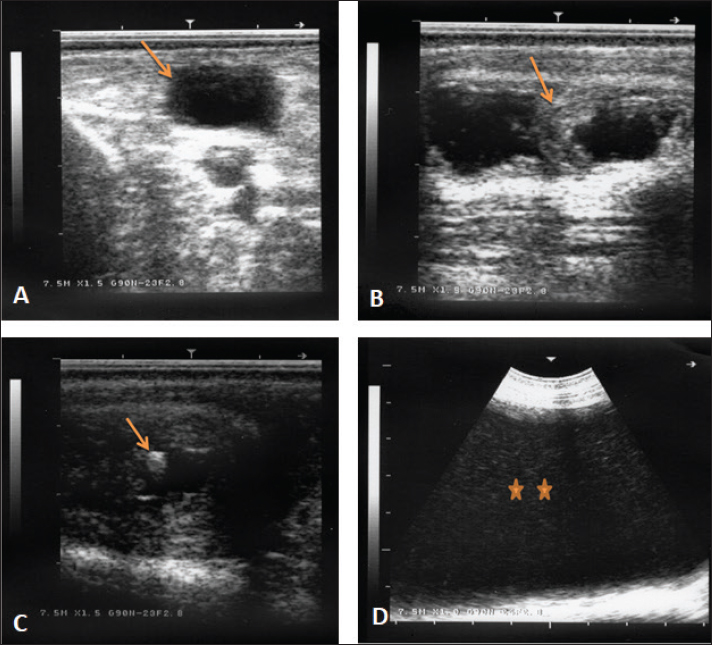

Fig. 6. Ultrasonographic finding in a buck with ruptured bladder due to urethral obstruction by a calculus. Image (A) shows a ruptured and collapsed urinary bladder within the pelvic cavity (arrow). Image (B) shows a dilated urethra with increased wall thickness (arrow). Image (C) shows a calculus within the urethra characterized by acoustic enhancement with distal acoustic shadowing (arrow). Image (D) shows massive abdominal effusions (stars).

Table 1 shows also the sonographic results of the rams and bucks with red urine. These findings included ruptured urinary bladder in 3 (16.7%) (Fig. 6), ruptured urethra in 5 (27.8%) (Figs. 4 and 5), penile calculi in 4 (22.2%) (Fig. 6), uroperitoneum in 6 (33.3%) (Figs. 1 and 6), distended urinary bladder in 7 (38.9%) (Fig. 1), hydronephrosis in 5 (27.8%) (Fig. 2), echogenic deposits in the bladder in 3 (16.7%) (Fig. 3), and ventral urine accumulation in 4 (22.2%) animals (Fig. 5). Laboratory evaluation of a Geimsa-stained blood smear confirmed the infection with B. ovis in three bucks and a ram (Fig. 7). Hemolytic anemia was marked in two bucks and a ram due to chronic copper toxicity (Fig. 8).

In small ruminants, ultrasonography provides the field veterinarian with immediate, non-invasive, and inexpensive results about the general condition of the animals. Through repeat scanning, the clinician can also visualize the progression of the disease and can ass the treatment effectiveness (Scott, 2016). In addition, ultrasonographic evaluation of the urinary system in sheep and goats was documented to be a highly valuable technique. It is especially important for the early detection of renal disorders and their progression, expecting the prognosis and treatment follow-up in different urinary disorders (Tharwat, 2021a, b). During the current investigation, ultrasonography was very helpful in rams and bucks affected with red urine syndrome due to urolithiasis, babesiosis, and copper toxicosis. The technique was especially helpful in verification cases with ruptured urinary bladder, ruptured urethra, urethral calculi, uroperitoneum, distended urinary bladder, hydronephrosis, detection of echogenic deposits in the bladder, and evaluation of the extension of urine in the ventral abdominal region.